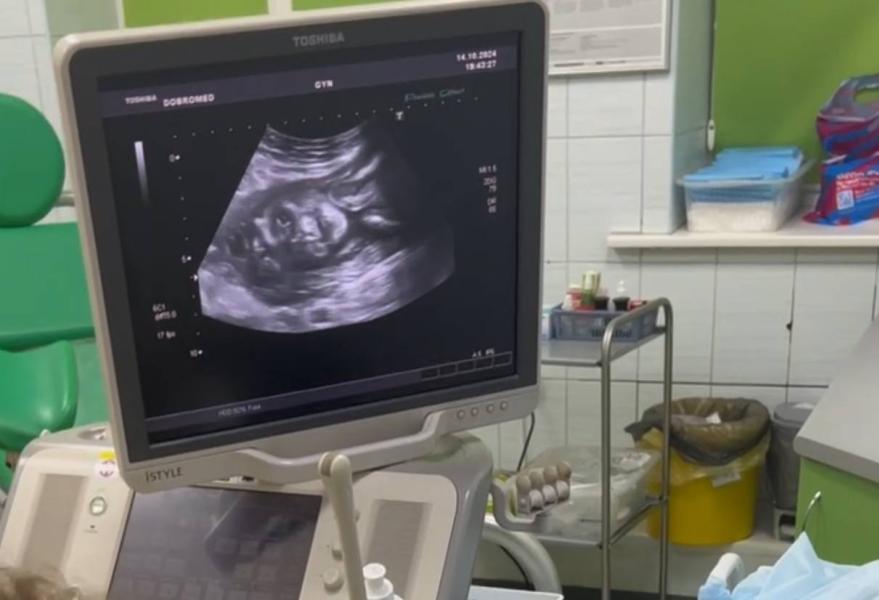

Какой вес у малыша на 22 неделе беременности?

22 недели -520 грамм +-🥰✊

На узи улыбался лежал)) фотка конечно треш🤣🤣🤣🤣